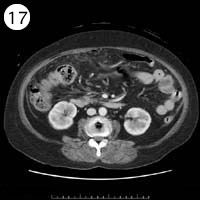

57歳 女性

単純CT

造影CT